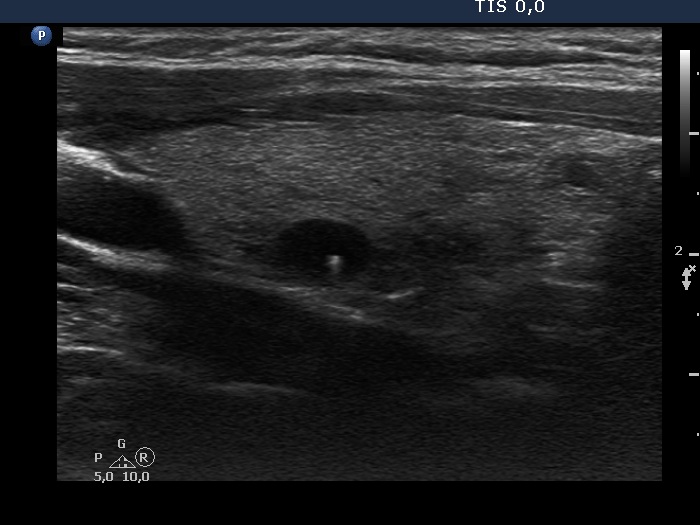

Ultrasonography. The thyroid was composed of numerous discrete lesions of various echogenicities. There was a partly cystic nodule in the upper-ventral part of the right lobe. The left lobe contained several cystic areas having comet tail artifacts.

Comment. The distinction between a cystic nodule and a cystic area is based on the size and the sum of the lesion and on the internal content. If the latter suggest a pure cyst in multiple lesions smaller than 1 cm in maximal diameter, than the lesions are very likely not true nodules but dilated macrofollicles.